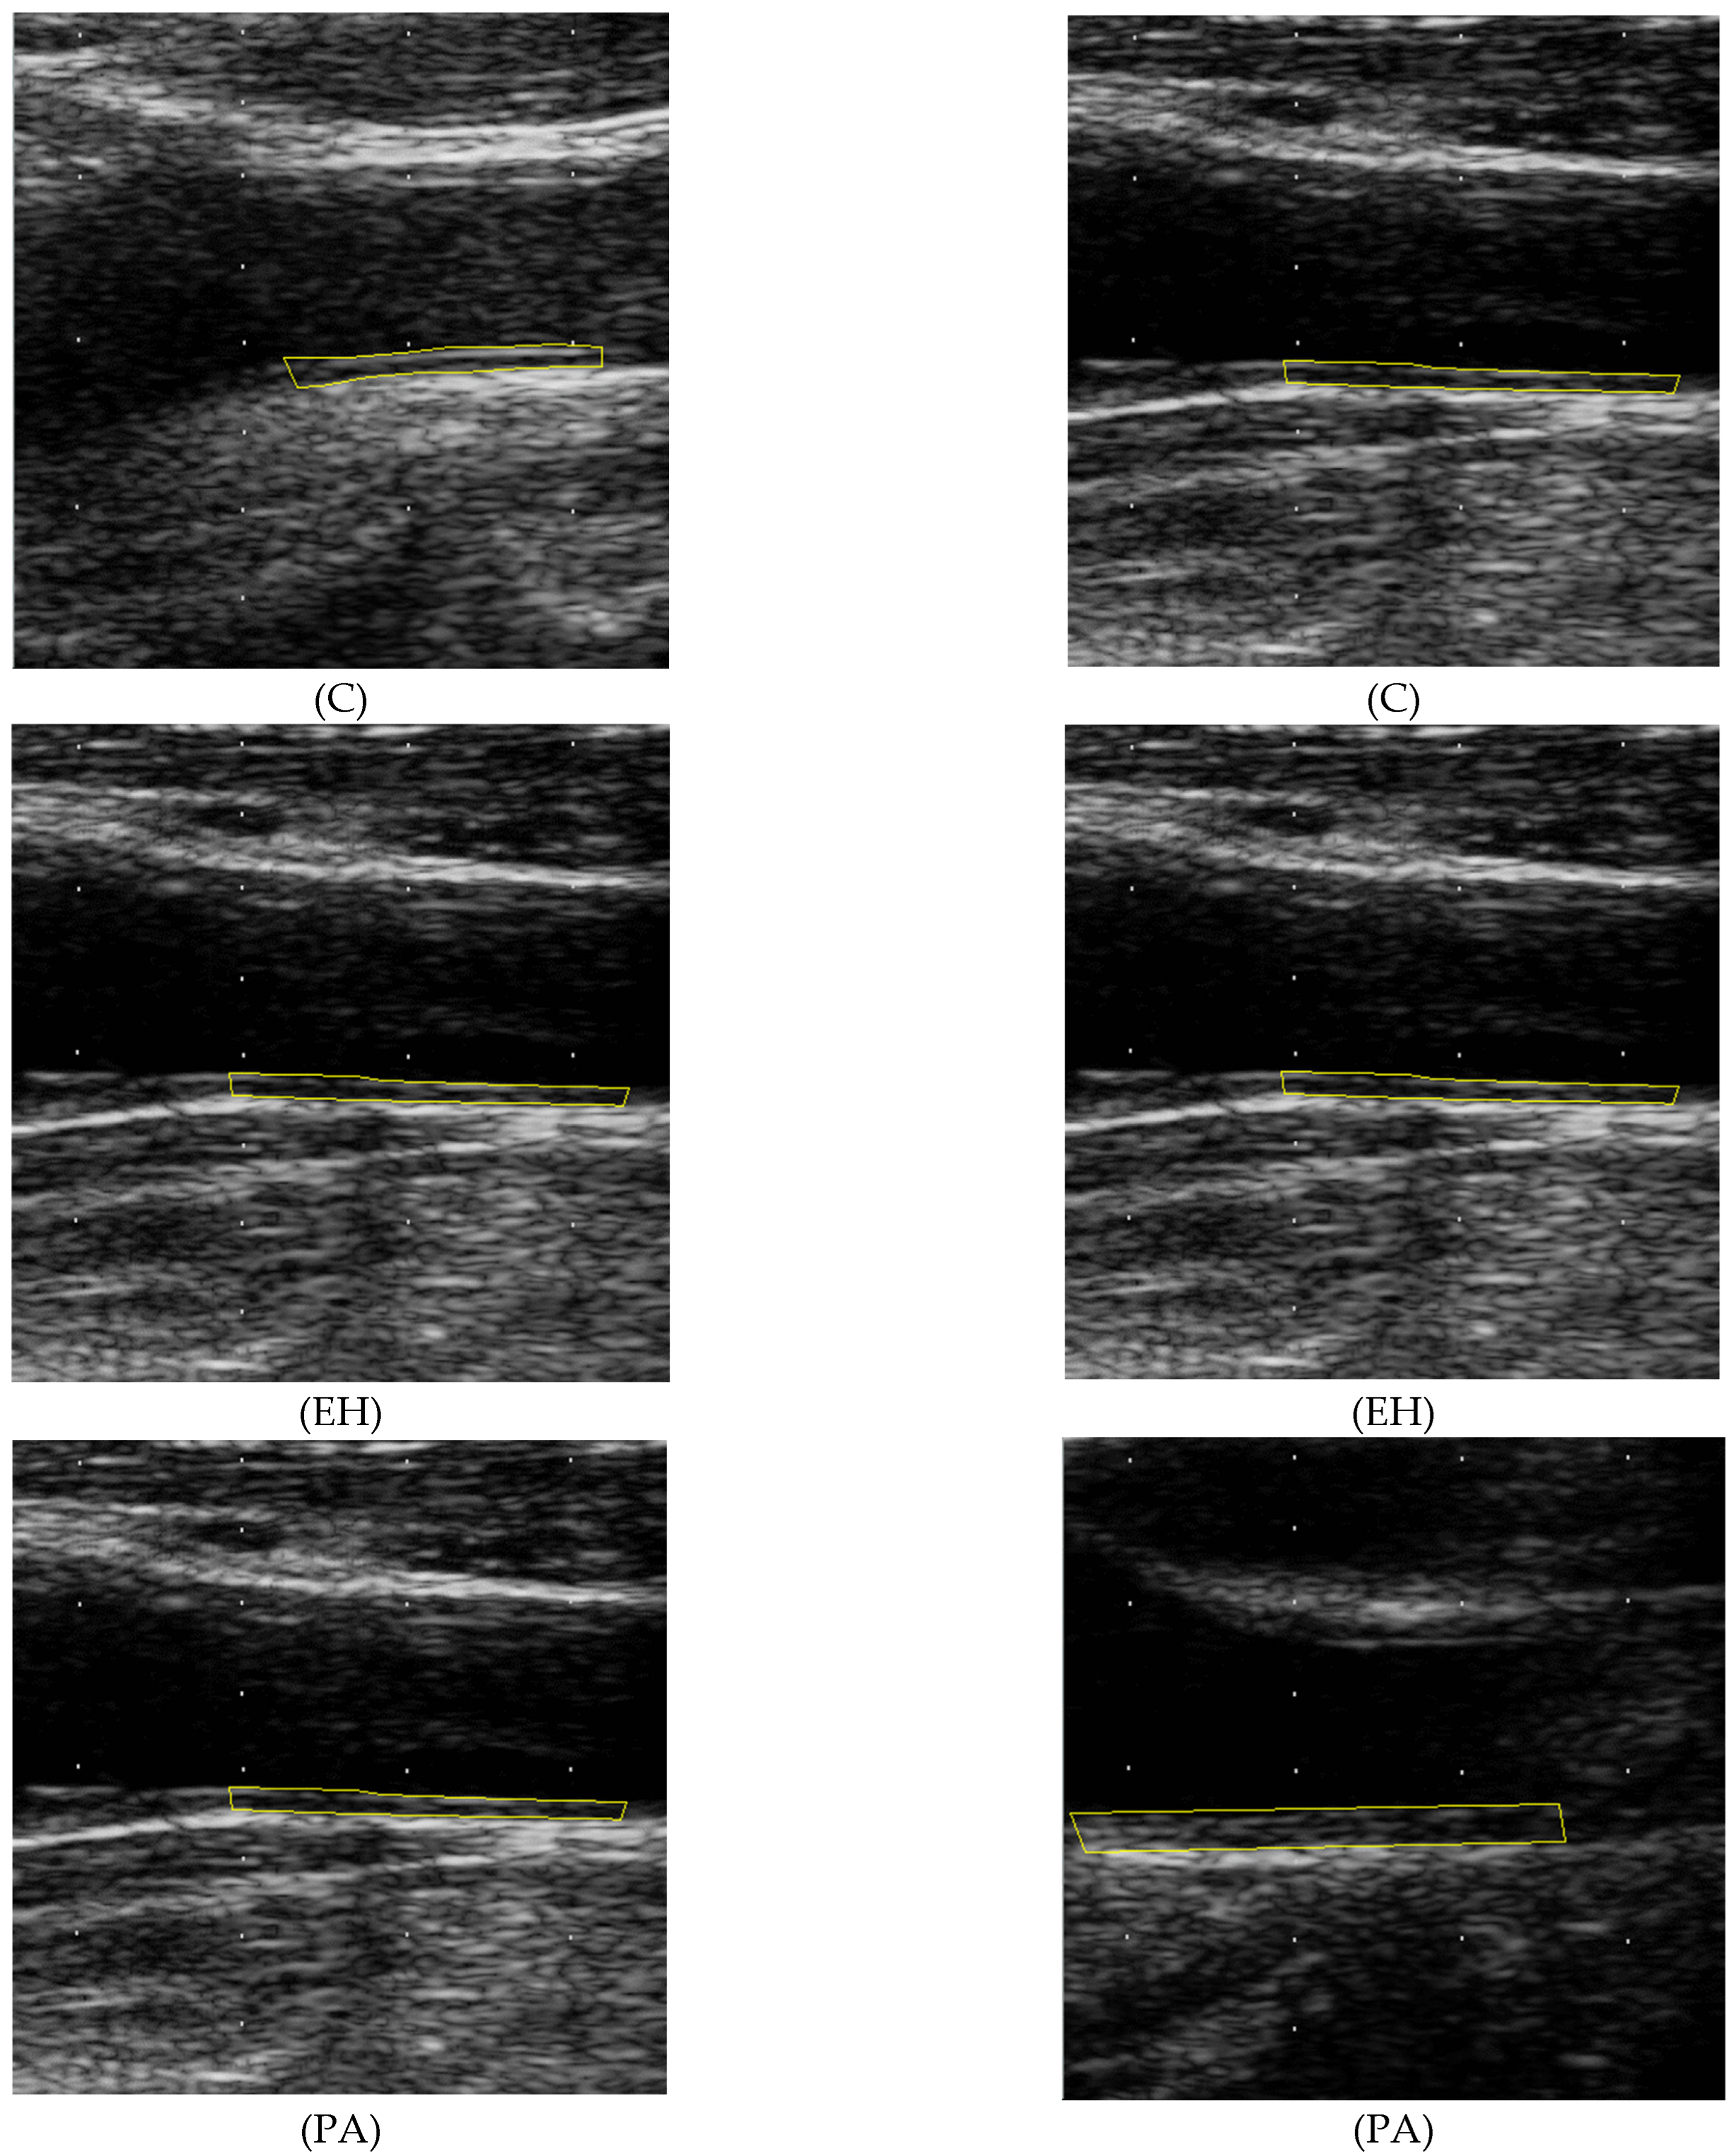

2.5. Texture Analysis